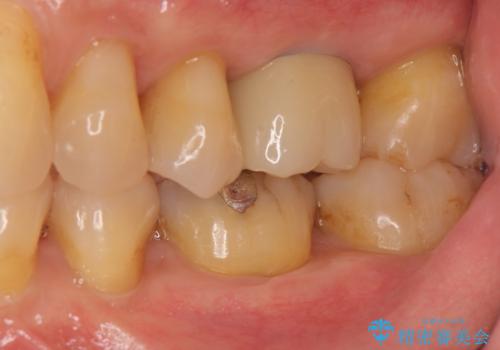

失った咬合機能の回復 インプラント治療

- 44万円(インプラント・チタンカスタムアバットメント・ジルコニアクラウン・仮歯)費用は治療当時の料金となります

歯が割れるほどの咬合力が強い方でしたので、3本の歯を2本で支えるブリッジではなく、咬合負担能力の増えるインプラント治療にメリットが大きいと言えます。